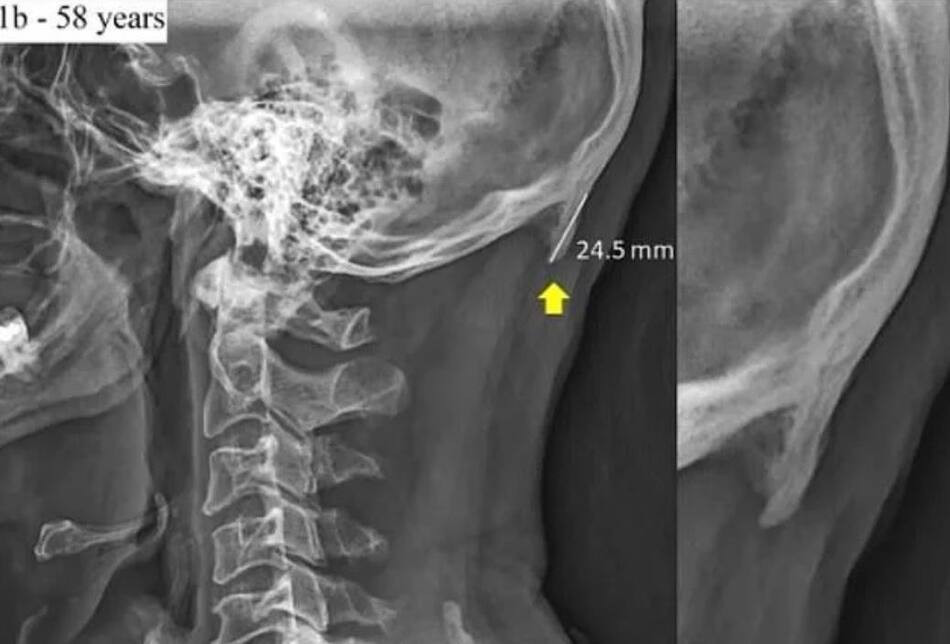

La estructura ósea trata de adaptarse para sostener mejor nuestra cabeza. La prueba está en las imágenes de rayos X publicadas por investigadores australianos. La cabeza de adulto promedio puede pesar alrededor de 5 kilogramos.

Los crecimientos llamados protuberancias occipitales externas agrandadas, se encuentran en la parte inferior del cráneo.